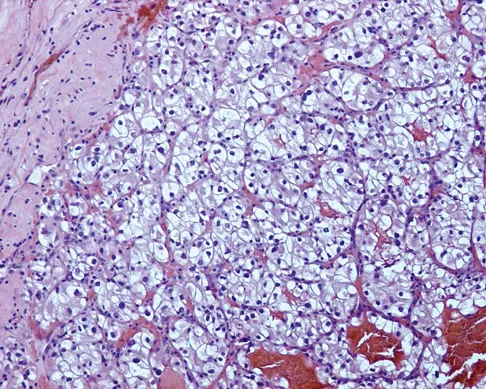

Figures 12a through 12e show the radiograph, MRI scans, and biopsy specimens of a 17-year-old boy. What is the most likely diagnosis?

The images show an epiphyseal lesion. The MRI scan shows extensive bone edema surrounding the lesion, consistent with chondroblastoma. Histology shows polygonal chondroblasts in a cobblestone-like pattern and areas of calcification consistent with chondroblastoma. Although some giant cells are seen, the age of the patient and the polygonal chondroblasts differentiate this lesion from giant cell tumor. Clear cell chondrosarcoma is an epiphyseal lesion that occurs in an older population, and the cells have clear cytoplasm. This lesion is not producing bone on imaging or histologic specimen, eliminating osteosarcoma. Tuberculous septic arthritis can be an epiphyseal lesion, but granulomas would be seen on histology. Menendez LR (ed): Orthopaedic Knowledge Update: Musculoskeletal Tumors. Rosemont, IL, American Academy of Orthopaedic Surgeons, 2002, pp 103-111.